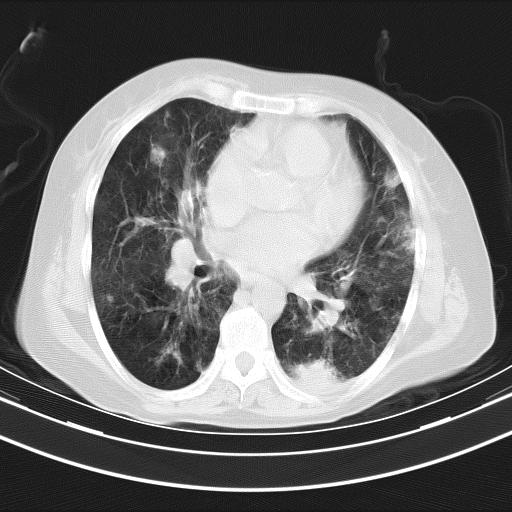

老年女性,嗜睡3天,意识模糊。轻咳,无发热。

两肺慢支炎伴感染,左侧胸腔积液。纵膈及双侧肺门淋巴结肿大建议复查。

双肺多发淡片影,毛玻璃影,,支持支气管肺炎,,建议血气找原因,,嗜睡是否肺性脑病?有没有慢支病史?

双肺炎症,建议抗炎治疗后复查,见过几个老年肺炎病例,没有发烧、咳嗽症状,直接以昏迷就诊。

1)两肺感染性病变;建议抗炎治疗后复查。2)纵隔淋巴结肿大。3)左侧胸腔积液。